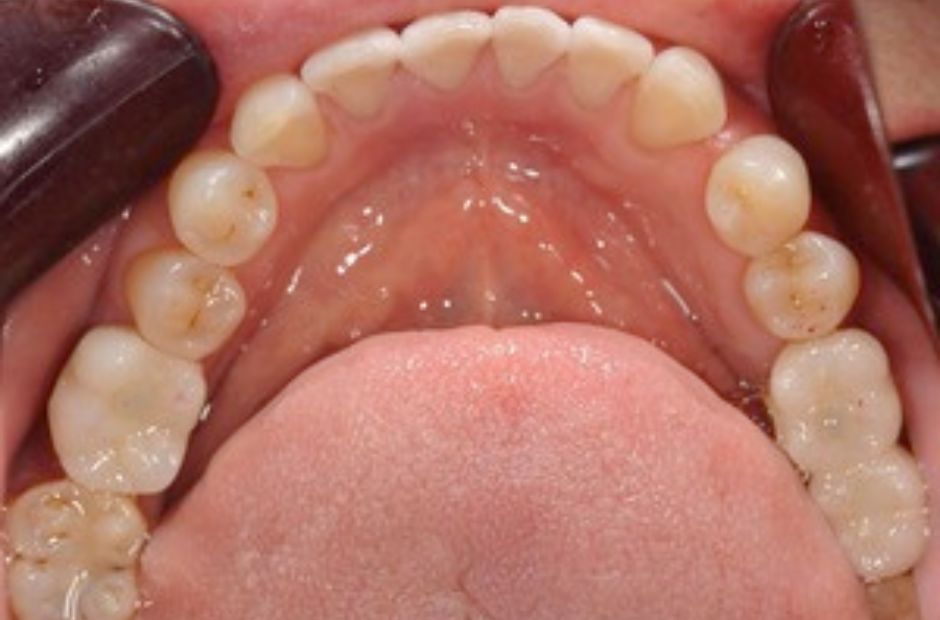

case.04

他院で断られた症例の成功

他院でインプラント治療が困難とされた高齢の患者様が当院に来院されました。複雑な口腔状況でしたが、当院の専門知識と技術を活用してインプラント治療を成功させました。治療により、患者様は再び快適な食事と明確な発音を取り戻すことができました。